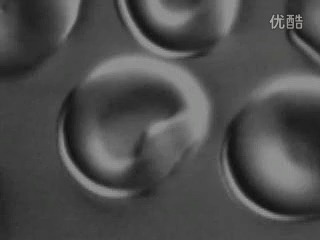

红细胞吸水涨破

细胞吸水过程 视频素材